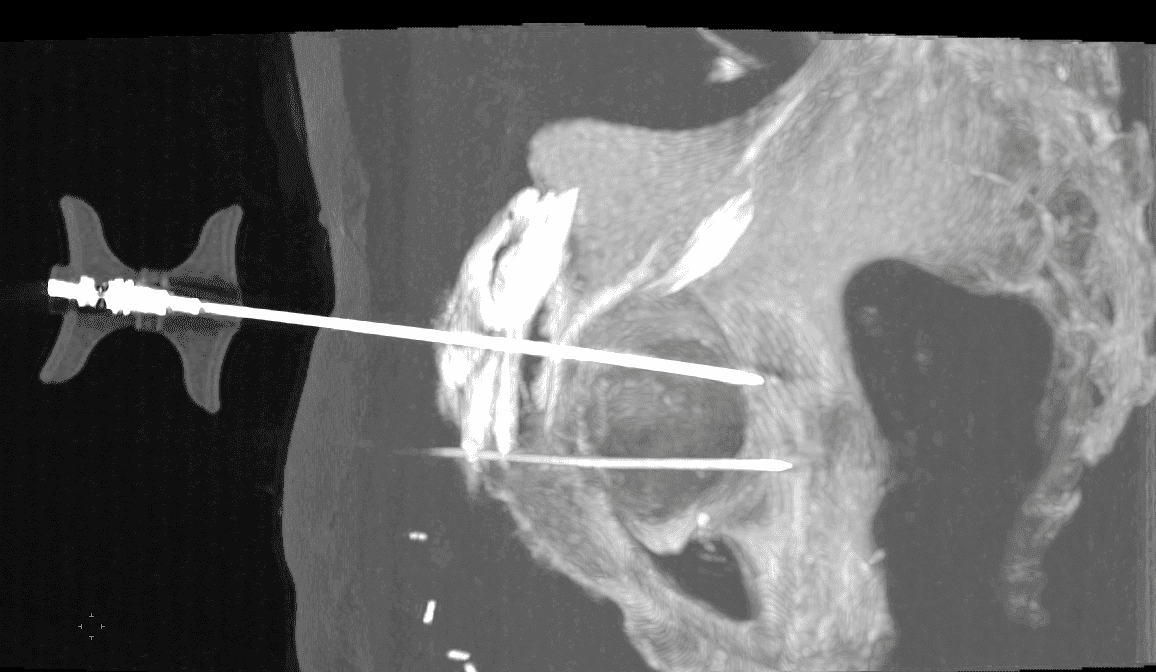

CT

L'implant SPINEJACK vise à réduire la fracture in situ par restauration de la hauteur anatomique du corps vertébral.

Technique de traitement des fractures vertébrales ostéoporotiques